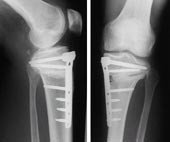

Umstellungsosteotomie:

In manchen Fällen ist der Knorpellverschleiß  entweder auf das innere oder

äußere Areal beschränkt. Dies geschieht häufig bei langjährigen einseitigen

Belastungen des Gelenkes wie z.B. bei O- oder

X-Bein - Fehlstellungen oder auch nach Voroperationen bzw. nach bestimmten Gelenkbrüchen. In solchen Fällen wird abhängig vom Alter des Patienten und dem Beschwerdeausmaß die Geradestellung bzw. eine leichte Überkorrektur der Gelenkachse empfohlen mit dem Ziel, das geschädigte Gelenkareal zu entlasten und die Hauptbelastung auf das unverletzte Areal zu richten.